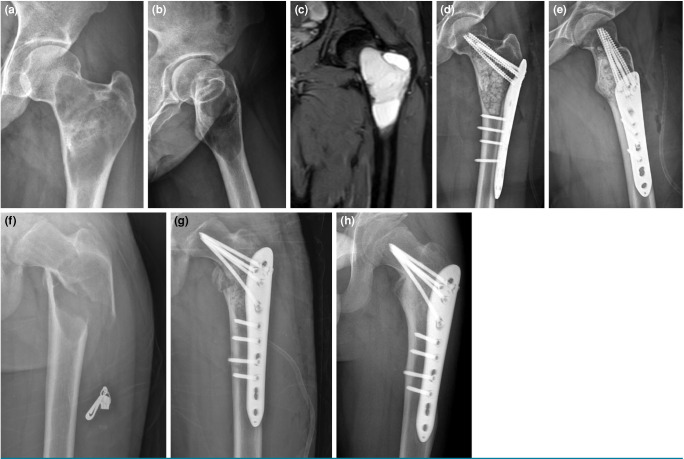

Patients and methods: Between January 2022 and June 2024, a total of 54 patients (23 males, 31 females; mean age: 35.2±14.5 years; range, 15 to 67 years) who underwent surgery for benign and benign-aggressive bone tumors in the lower extremities were retrospectively analyzed. Of the patients, 16 developed pathological fractures and 38 did not. Kinesiophobia was assessed using the Tampa Kinesiophobia Scale (TKS), and anxiety levels were measured using the State-Trait Anxiety Inventory (STAI-I and STAI-II).

Results: Pathological fractures occurred in 29.6% of cases. The most common tumor types were enchondroma (44.4%), giant cell tumor (18.5%), and aneurysmal bone cyst (11.2%). Patients with pathological fractures had significantly higher TKS, STAI-I, and STAI-II scores than those without fractures (p<0.001, p=0.034, and p<0.001, respectively).

Conclusion: In benign and benign-aggressive musculoskeletal lesions of the lower extremity, implementing prophylactic surgical intervention by predicting fracture risk reduces patients' levels of kinesiophobia and anxiety. Preventing pathological fractures in weight-bearing long bones allows for early mobilization, prevents fracture-related complications, and helps to preserve psychological well-being.